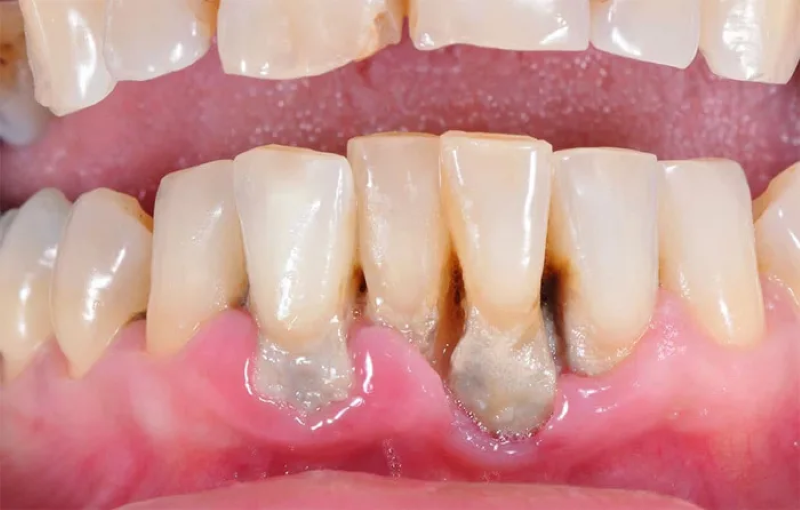

- Nướu tụt, cổ răng lộ dài hơn trước;

- Xuất hiện túi nha chu (khoảng trống giữa răng và nướu);

- Răng ê buốt, dịch mủ chảy ở kẽ nướu;

- Răng lung lay, xô lệch vị trí.